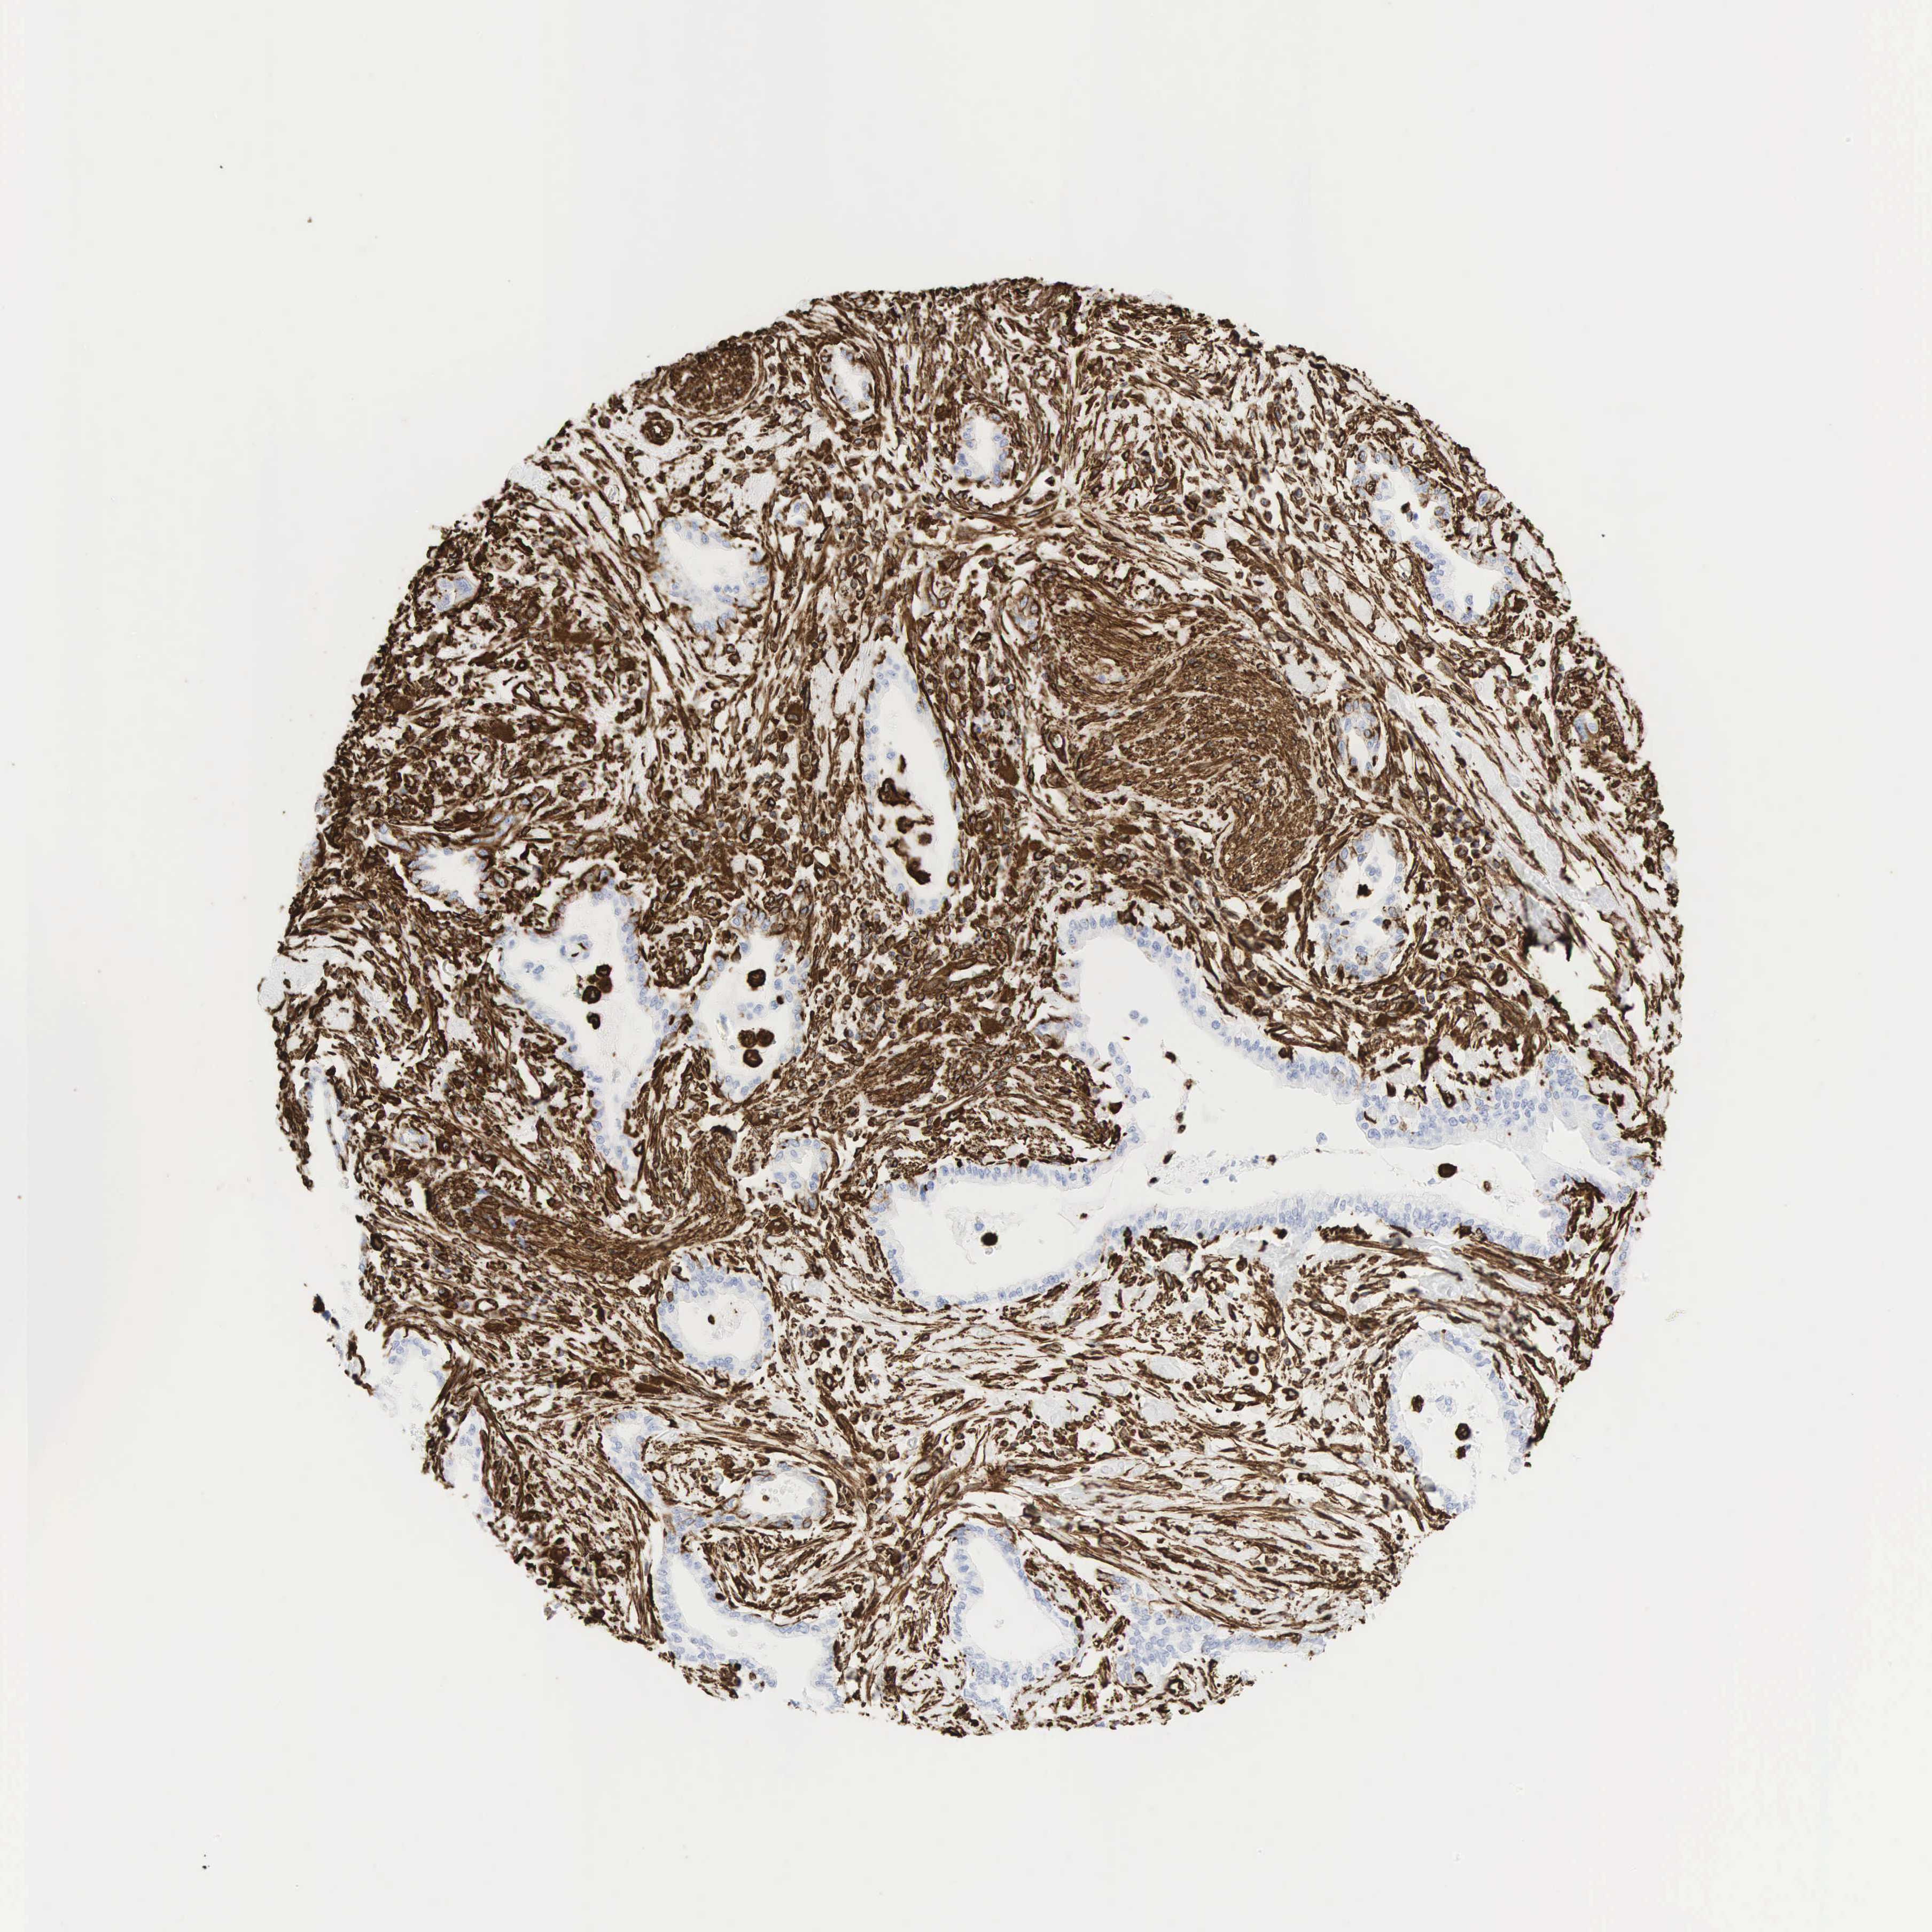

PANCREATIC CANCER - Protein expressioni

A mouse-over function shows sample information and annotation data. Click on an image to view it in a full screen mode. Samples can be filtered based on level of antibody staining by selecting one or several of the following categories: high, medium, low and not detected. The assay and annotation is described here.

Note that samples used for immunohistochemistry by the Human Protein Atlas do not correspond to samples in the TCGA dataset.

Antibody stainingi

Antibody staining in the annotated cell types in the current human tissue is reported as not detected, low, medium, or high, based on conventional immunohistochemistry profiling in selected tissues. This score is based on the combination of the staining intensity and fraction of stained cells.

Each image is clickable and will lead to virtual microscopy that enables deeper exploration of all samples and also displays staining intensity scores, fraction scores and subcellular localization as well as patient and tissue information for each sample.

Antibody HPA001762

Antibody CAB000080

Antibody CAB058687

Staining

High

Medium

Low

Not detected

Intensity

Strong

Moderate

Weak

Negative

Quantity

>75%

75%-25%

<25%

None

Location

Nuclear

Cytoplasmic/membranous

Cytoplasmic/membranous,nuclear

Adenocarcinoma, NOS

Adenocarcinoma, metastatic, NOS